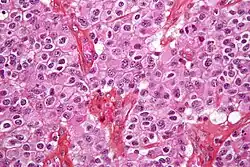

Histologie

Die Tumorzellen wachsen teils diffus ins Gewebe ein und teils nodulär. Mikroskopisch erkennt man optisch leere Räume um die Zellkerne, ein sogenanntes typisches „Spiegelei-“ oder „Honigwabenmuster“ – ein Artefakt aus der histologischen Aufarbeitung. Weiterhin erkennt man sehr gleichförmige runde Zellkerne und langgezogene gerade Kapillaren.[4]

Zellteilungen sind bei Grad 2 höchstens vereinzelt sichtbar, der Proliferationsmarker Ki-67 ist meist bei weniger als fünf Prozent der Zellen positiv. Grad 3 zeigt häufigere Mitosen und meist mehr als zehn Prozent Ki-67-positive Zellen.[4]

Im Gegensatz zu anderen diffusen Gliomen zeigen Oligodendrogliome besonders häufig (Mikro-)Verkalkungen. Teilweise finden sich auch muzinöse, mikrozystische oder bindegewebliche Abschnitte.[4]